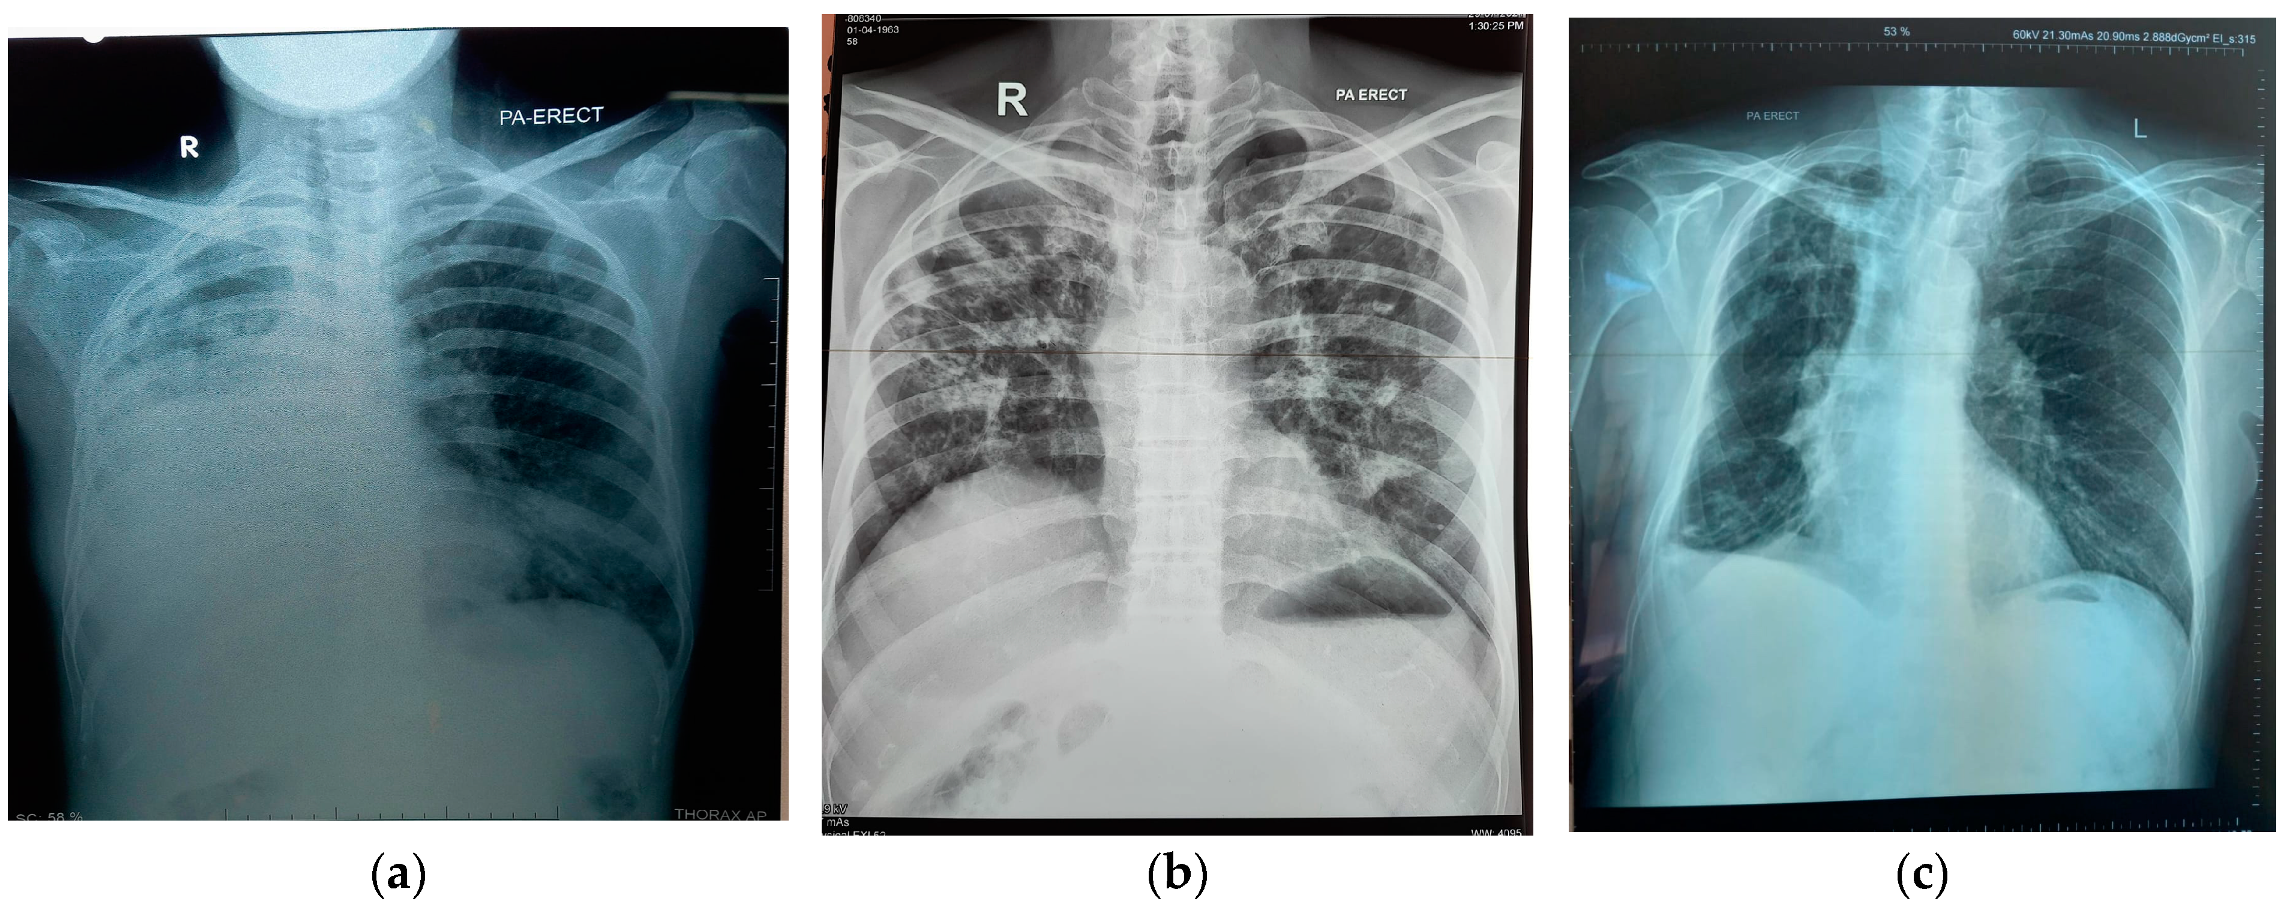

Patients with detectable antibodies tended to have worse disease. So, 8 of 14 (57.1%) of those with positive Histoplasma antibodies had far advanced radiological appearances as did 8 (50%) of those with Aspergillus antibody (Figure 1). However, there was no statistical association between severity of chest X-ray appearance and having a positive Histoplasma or Aspergillus antibody result (p = 0.069 and 0.48, respectively). The criteria for the diagnosis of CPH and CPA were fulfilled in those with moderately and far advanced disease (13 of 14 (92.9%) and 12 of 16 (75%), respectively).

Figure 1.

Chest X-ray examples in cases of chronic pulmonary histoplasmosis and aspergillosis: (a,b) far advanced radiological findings, (c) moderately advanced radiological findings.

There were no deaths in the MDR-TB group who did not have antibodies against either H. capsulatum or Aspergillus fumigatus. In the group with a positive H. capsulatum antibody result, one person died two months after diagnosis of MDR-TB and a month after detection of Histoplasma antibodies. Two individuals in the group with positive Aspergillus antibodies died two and five months after MDR-TB was diagnosed. Furthermore, one individual who had both antibodies also died three months after the diagnosis of MDR-TB was established (Figure 2). All patients passed away during treatment for MDR-TB; two of them had diabetes mellitus. All four patients had advanced radiological images according to the established criteria, with the female patient who tested positive for both Aspergillus and Histoplasma antibodies having the most severe lung radiological images compared to the other three patients. That patient had extensive infiltrate in both lungs, and the right lung had collapsed (Figure 1a). Meanwhile, three other patients, although they had extensive infiltrate in both lungs, had no collapsed lungs. The proportion dying with positive fungal antibodies was not significant compared with those without antibodies (p = 0.11).